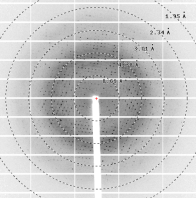

▶结晶和结构解析(周期:1-2周)